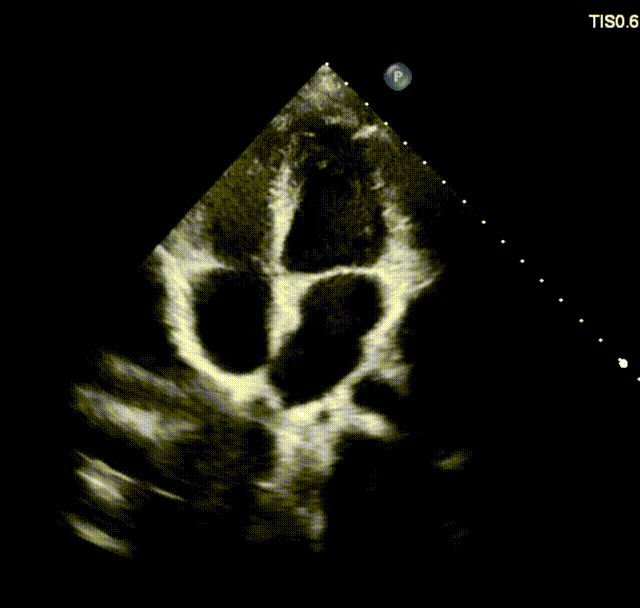

室早RFCA+ASD介入病例(上:术后6个月心超;下:术后12个月心超)

上述良好的短中期随访结果验证了可降解封堵器在儿童ASD介入治疗中的安全性与有效性,期待更长期的随访数据进一步验证远期效果。